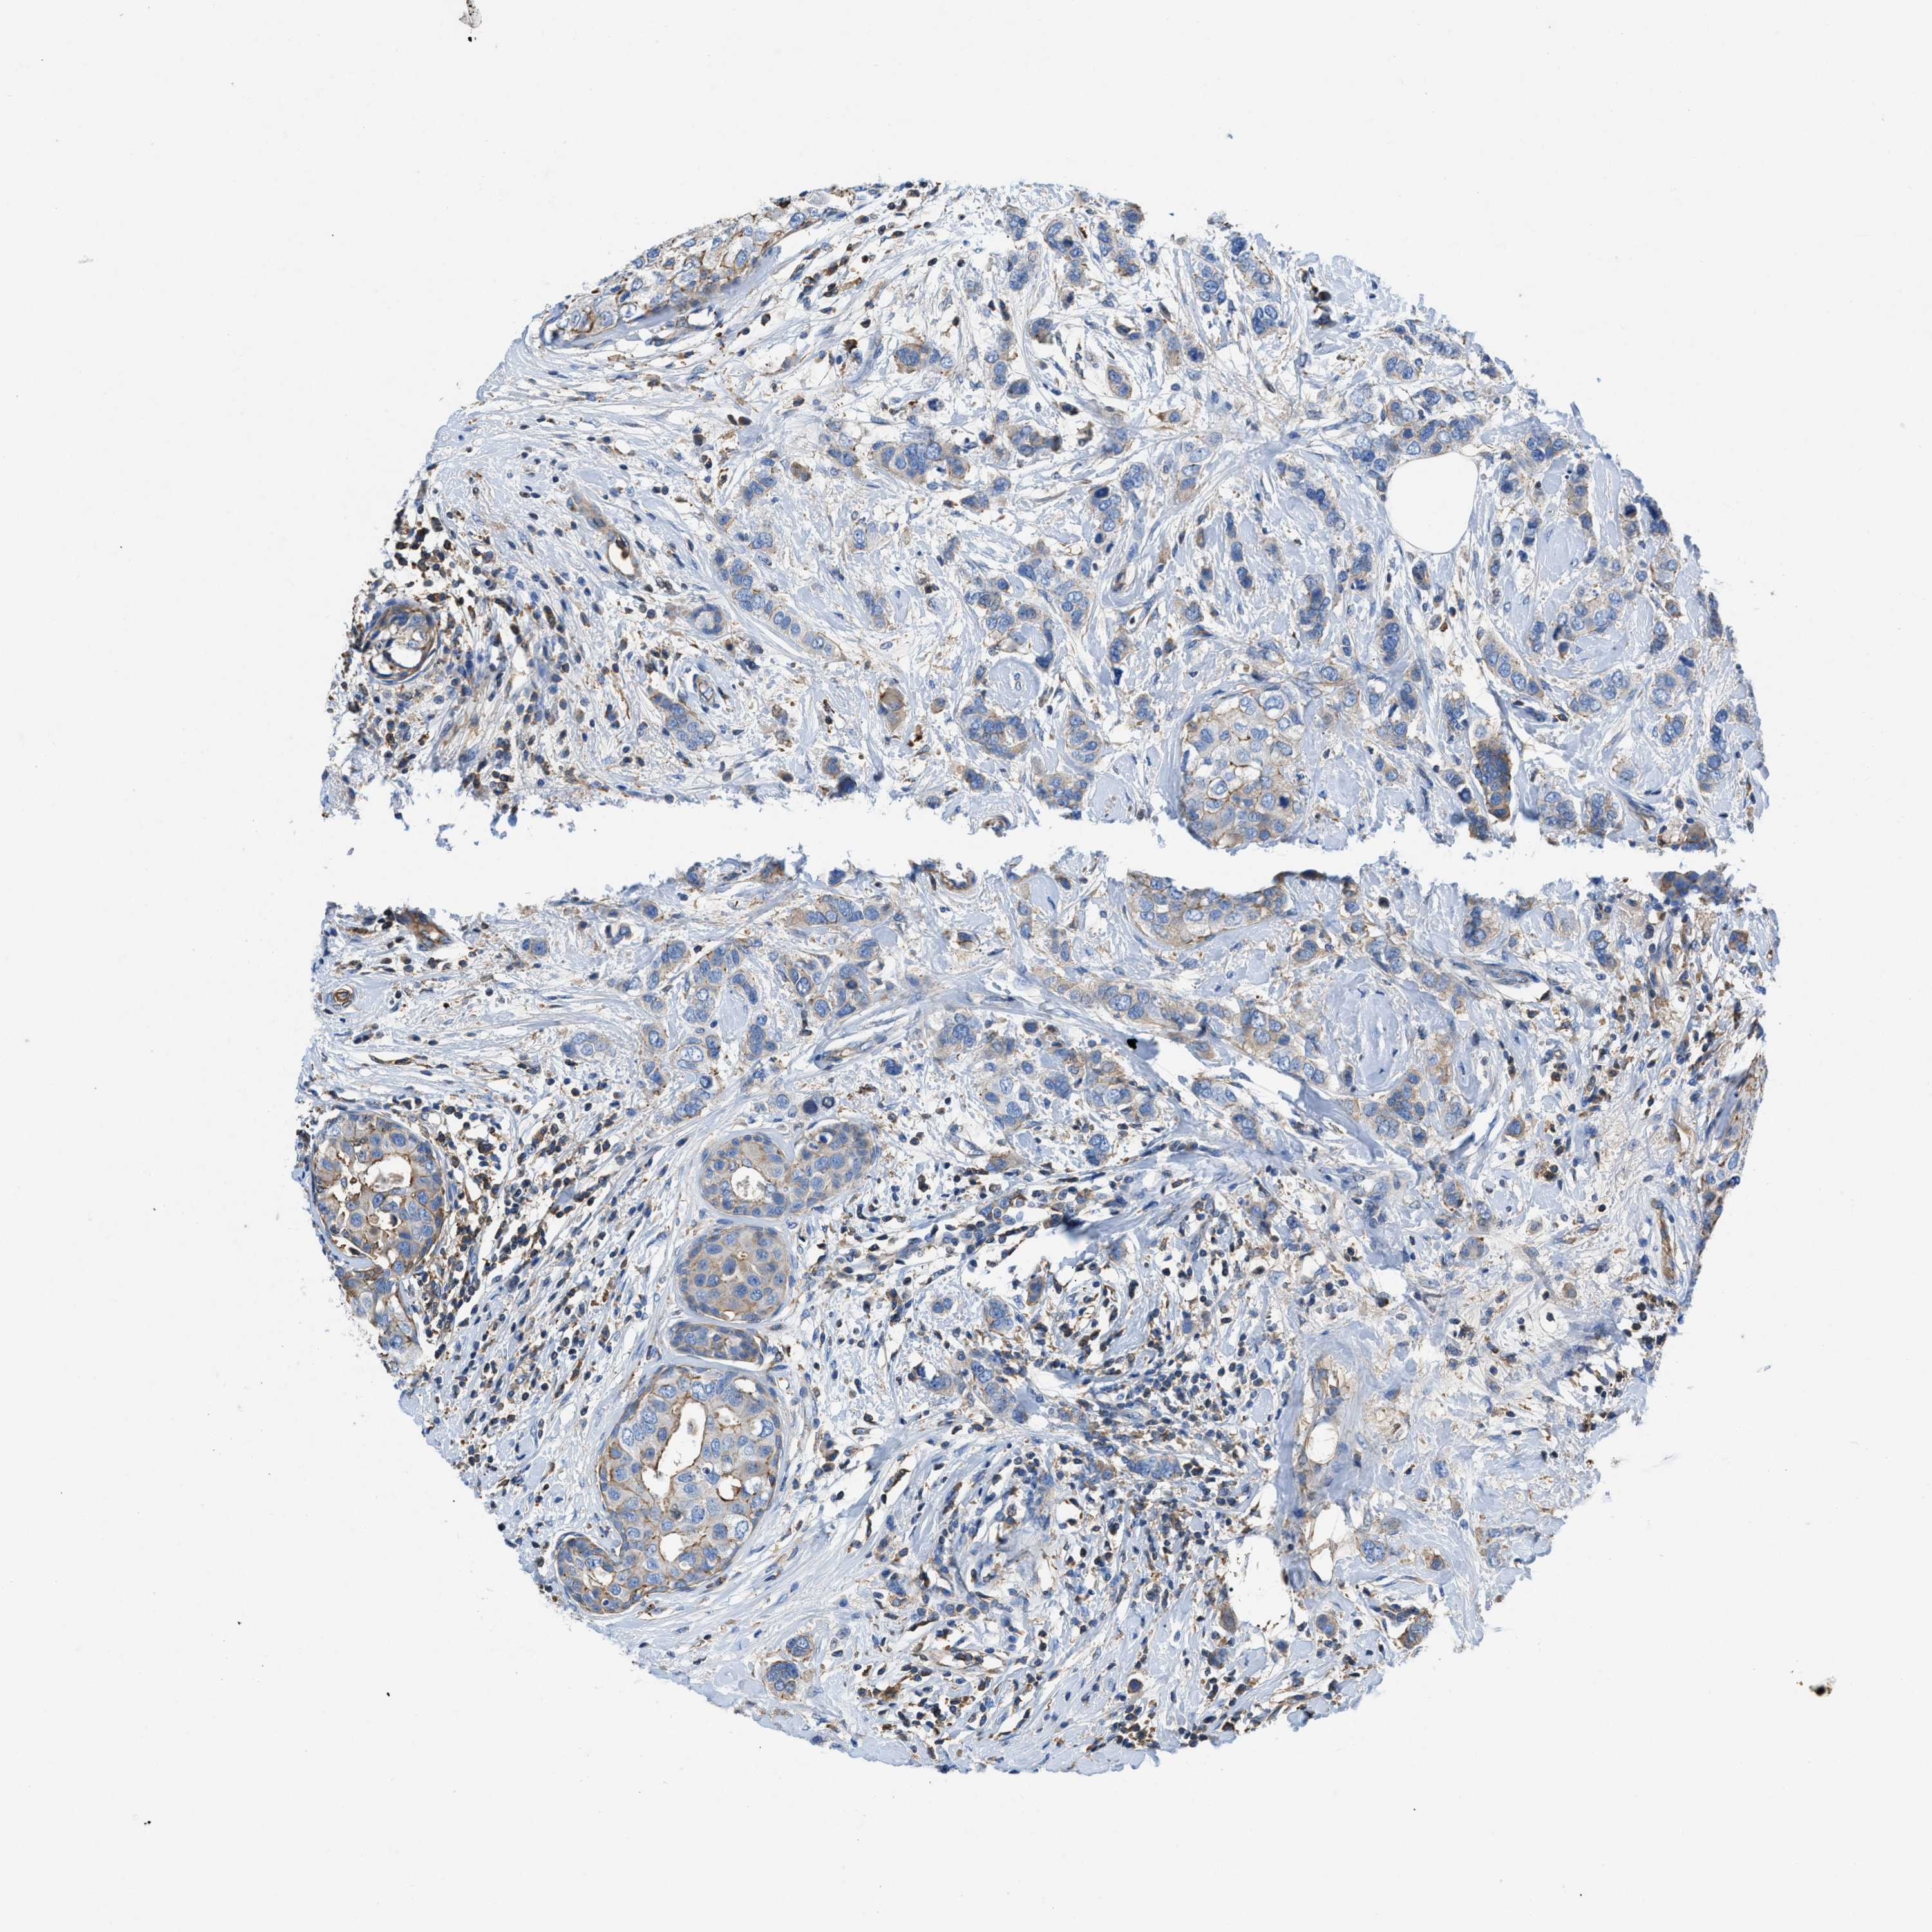

CANCER BREAST CANCER Show tissue menu

BRCA TCGA BRCA VALIDATION PROTEIN EXPRESSION

Breast cancer

Human cancer

ATP6V0D1 is potential prognostic, high expression is unfavorable in Breast Invasive Carcinoma (TCGA)